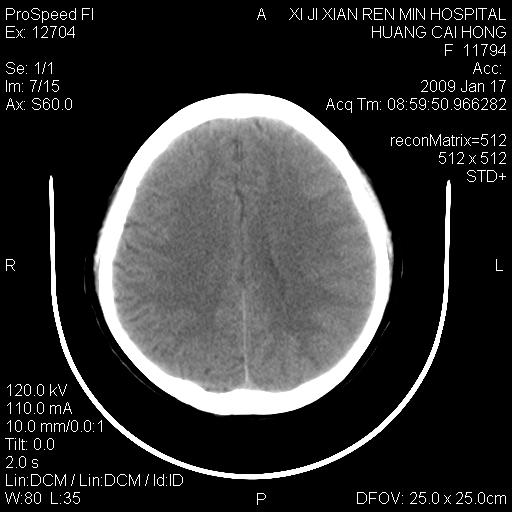

以下是引用zbp537在2009-1-19 13:54:00的发言:[br]首先考虑脑炎。[br]诊断依据:[br]1、患者较年轻。[br]2、有感冒病史。[br]3、左侧颞枕叶这么大一片低密度影,占位征象却不明显,不符合肿瘤特征,其内的高密度影为出血灶。

以下是引用xiaoniu在2009-1-19 13:29:00的发言:[br]左侧颞叶三角形低密度影,占位效应不明显,其内点片样高密都影,青少年患者,首先考虑:少突胶质瘤。因为有感冒病史,不能除外感染的可能。